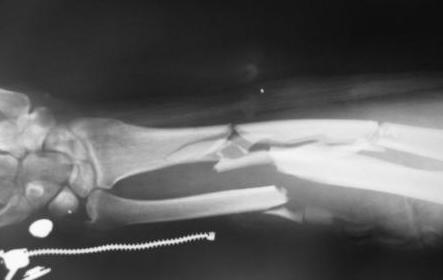

Больной был прооперирован 22.12.08 г. Выполнено: открытая репозиция локтевой кости, остеосинтез пластиной, открытая репозиция лучевой кости, остеосинтез пластиной, винтами, костная аутопластика. ВХО раны левого плеча. Открытая репозиция, остеосинтез мыщелка плеча пластиной винтами, по Веберу, костная аутопластика. Из особенностей операции можно отметить, что при остеосинтезе плечевой кости отсутствовал фрагмент, которым являлся блок плечевой кости. Данный фрагмент замещен аутокостью. Послеоперационное течение без осложнений. Больной выписан на амбулаторное лечение.

Прикладываю послеоперационные снимки.

Досылаю остальные снимки, вчера не смог их прикрепить из-за технических причин.

IMG_2647W.jpg